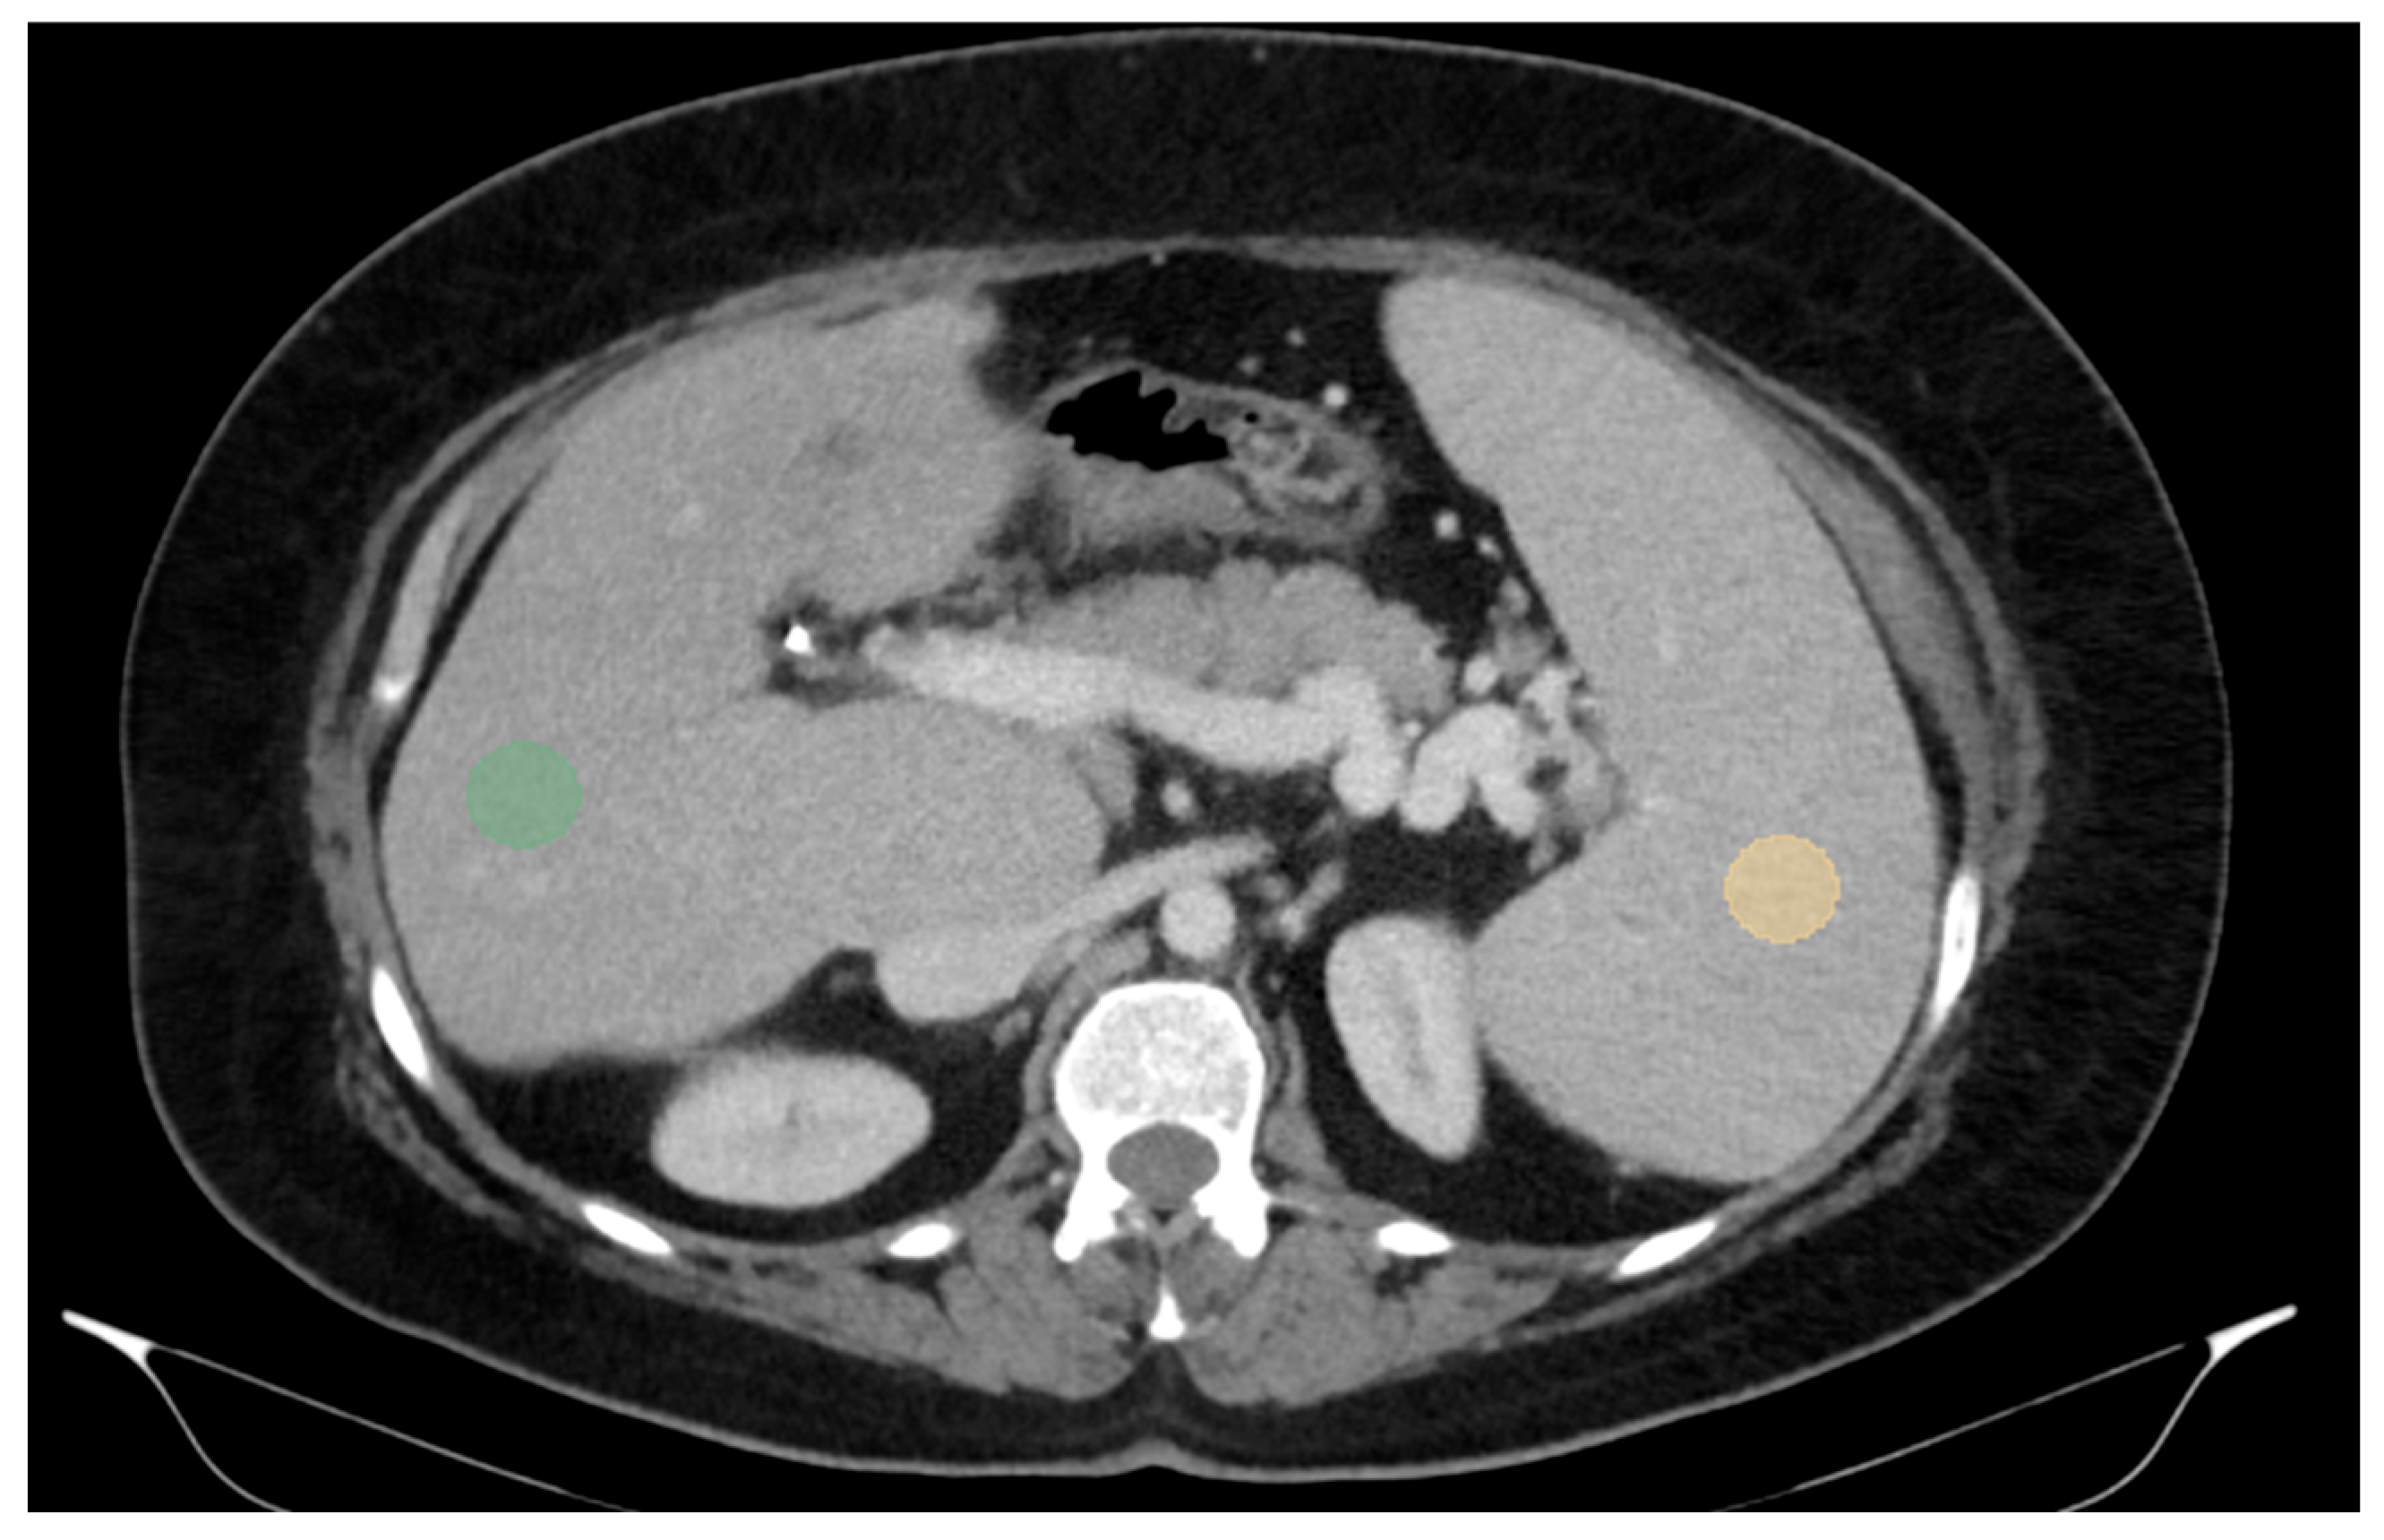

For three-dimensional (3D) segmentation, the TotalSegmentator module in Slicer was used for automated organ segmentation, followed by manual correction of the right and left portal vein, to ensure anatomical accuracy (Figure 2).

Figure 2.

Abdominal portal-venous-phase CT scan: axial, coronal, and sagittal planes (a–c). Example of 3D liver and spleen segmentations. Three-dimensional liver and spleen segmentations were performed by using the TotalSegmentator extension in Slicer software, followed by manual corrections. Images (a–c) show the liver and spleen segmentation in axial, coronal, and sagittal planes. Image (d) shows the final 3D segmentation of these organs.